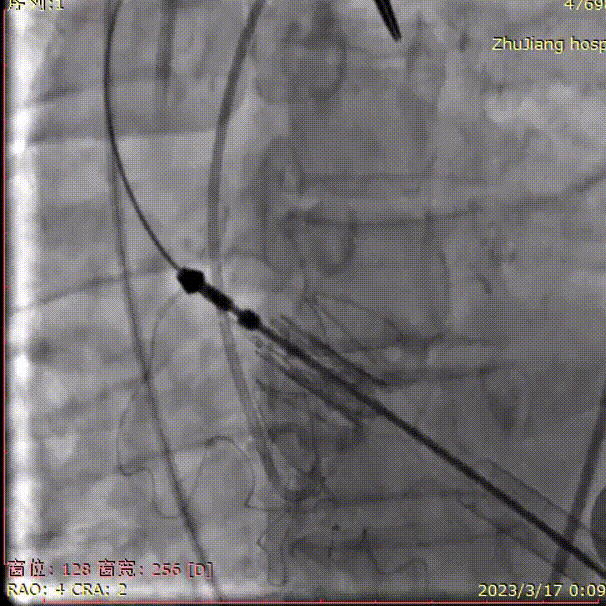

定位件入窦,瓣膜件下落到瓣环平面,造影确认位置:

释放瓣膜: